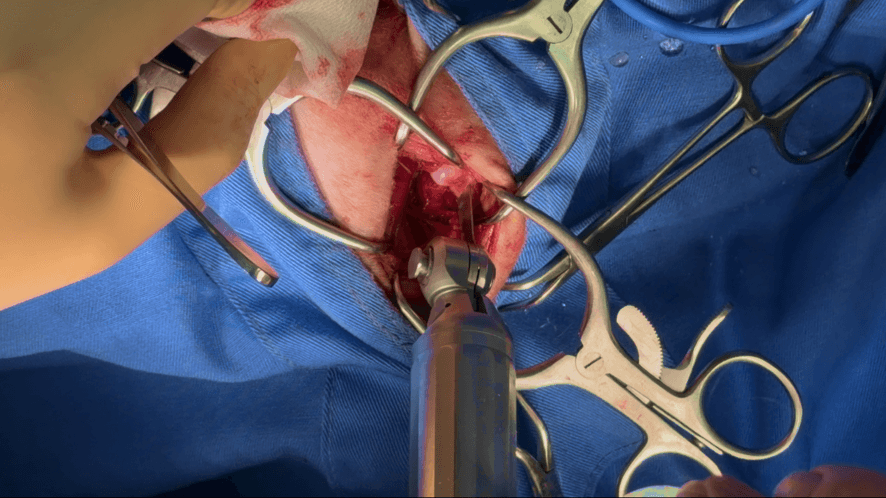

(いきなりですが...💦)側面の太もも付近から皮膚を切開し、筋肉を分けて今回の大腿骨頭の部位を露出させたら、電動のソーで切っていきます。

ちょうど切り離すところです。